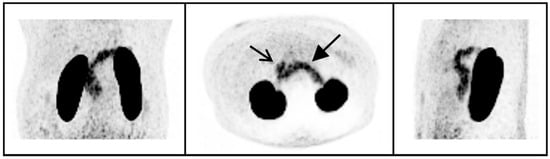

In peripheral organs, clear uptake of 68Ga-NODAGA-exendin-4 was visible in the pancreas (Figure 2), with an average SUVmean of 5.5 ± 1.8 (range 2.3–8.1) and SUVmax of 10.3 ± 3.0 (range: 5.0–15.5). In the blood pool, average SUVmean was 1.5 ± 0.23 and in background tissues highest uptake levels were measured in the liver (SUVmean: 0.67 ± 0.17) and lowest in subcutaneous adipose tissue (SUVmean: 0.20 ± 0.054).

In this study, we show that there is no significant uptake of 68Ga-NODAGA-exendin-4 in the brain (parts inside the blood–brain barrier; BBB) of subjects with obesity, although there is clear uptake in the pituitary. We also reproduce the accumulation of 68Ga-NODAGA-exendin-4 PET in the pancreas [31].

4.1. 68Ga-NODAGA-Exendin-4 Uptake in Peripheral Organs

We have confirmed the ability of 68Ga-NODAGA-exendin-4 to assess GLP-1 binding in the pancreas [31]. In line with this finding, other radiotracers derived from exendin showed the ability to visualize the GLP-1 receptor expression in the pancreas [30,34].

Figure 2. 68Ga-NODAGA-exendin-4 PET maximum intensity projections of the abdomen of one subject in a coronal, axial, and sagittal view (left, middle, and right panel, respectively). Uptake in the pancreas (closed arrow), duodenum (open arrow) and kidneys can be observed.